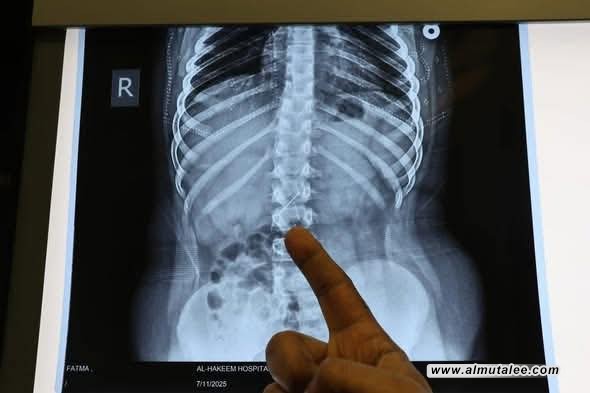

أجرى مستشفى الحكيم التعليمي في ميسان، اليوم الاثنين، عملية جراحية لاستخراج جسم غريب (أبرة خياطة) من أمعاء طفلة.

وذكر بيان لوزارة الصحة، تلقته المطلع، أن: “فريقا طبيا متخصصا في مستشفى الحكيم التعليمي التابع لدائرة صحة ميسان أجرى عملية جراحية لطفلة تبلغ من العمر (9) سنوات، تم خلالها استخراج جسم غريب (أبرة خياطة) كانت مستقرة داخل الأمعاء، وذلك بعد تشخيص دقيق للحالة وتدخل جراحي ناجح نفذه فريق جراحة الأطفال في المستشفى”.

وأكدت، أن: “العملية أُجريت بنجاح تام دون تسجيل أية مضاعفات”، مشيرة إلى أن: “الطفلة تتمتع حالياً بصحة جيدة، بفضل الجهود المتكاملة للفريق الطبي والتمريضي والصحي الساند وكادر التخدير في المستشفى”.